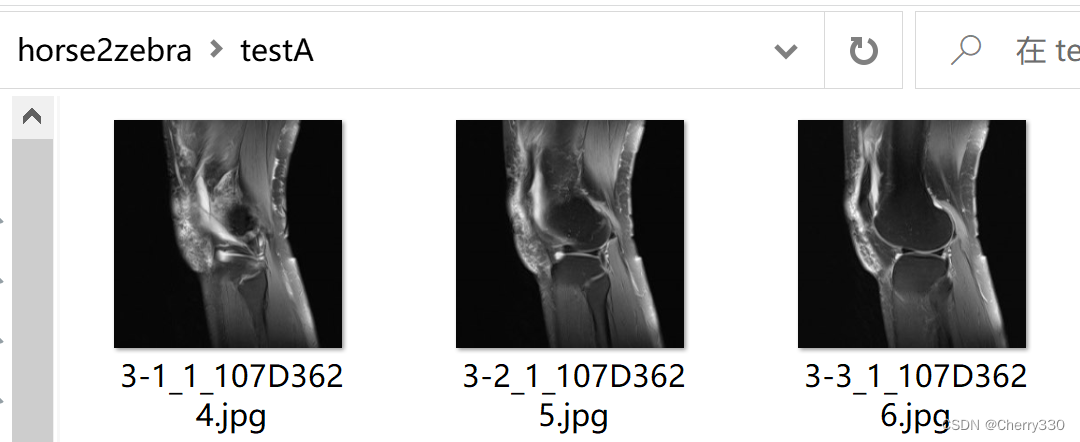

需要注意的是,trainA和trainB是训练的数据集,testA和testB是测试的数据集,大家记得按照自己需求进行分配哦~ trainA和testA是需要转换的图片,就是我做的这个的T2图片,trainB和testB是风格图片,就是我的任务中的T1图片。如图5。

图5 数据集构成